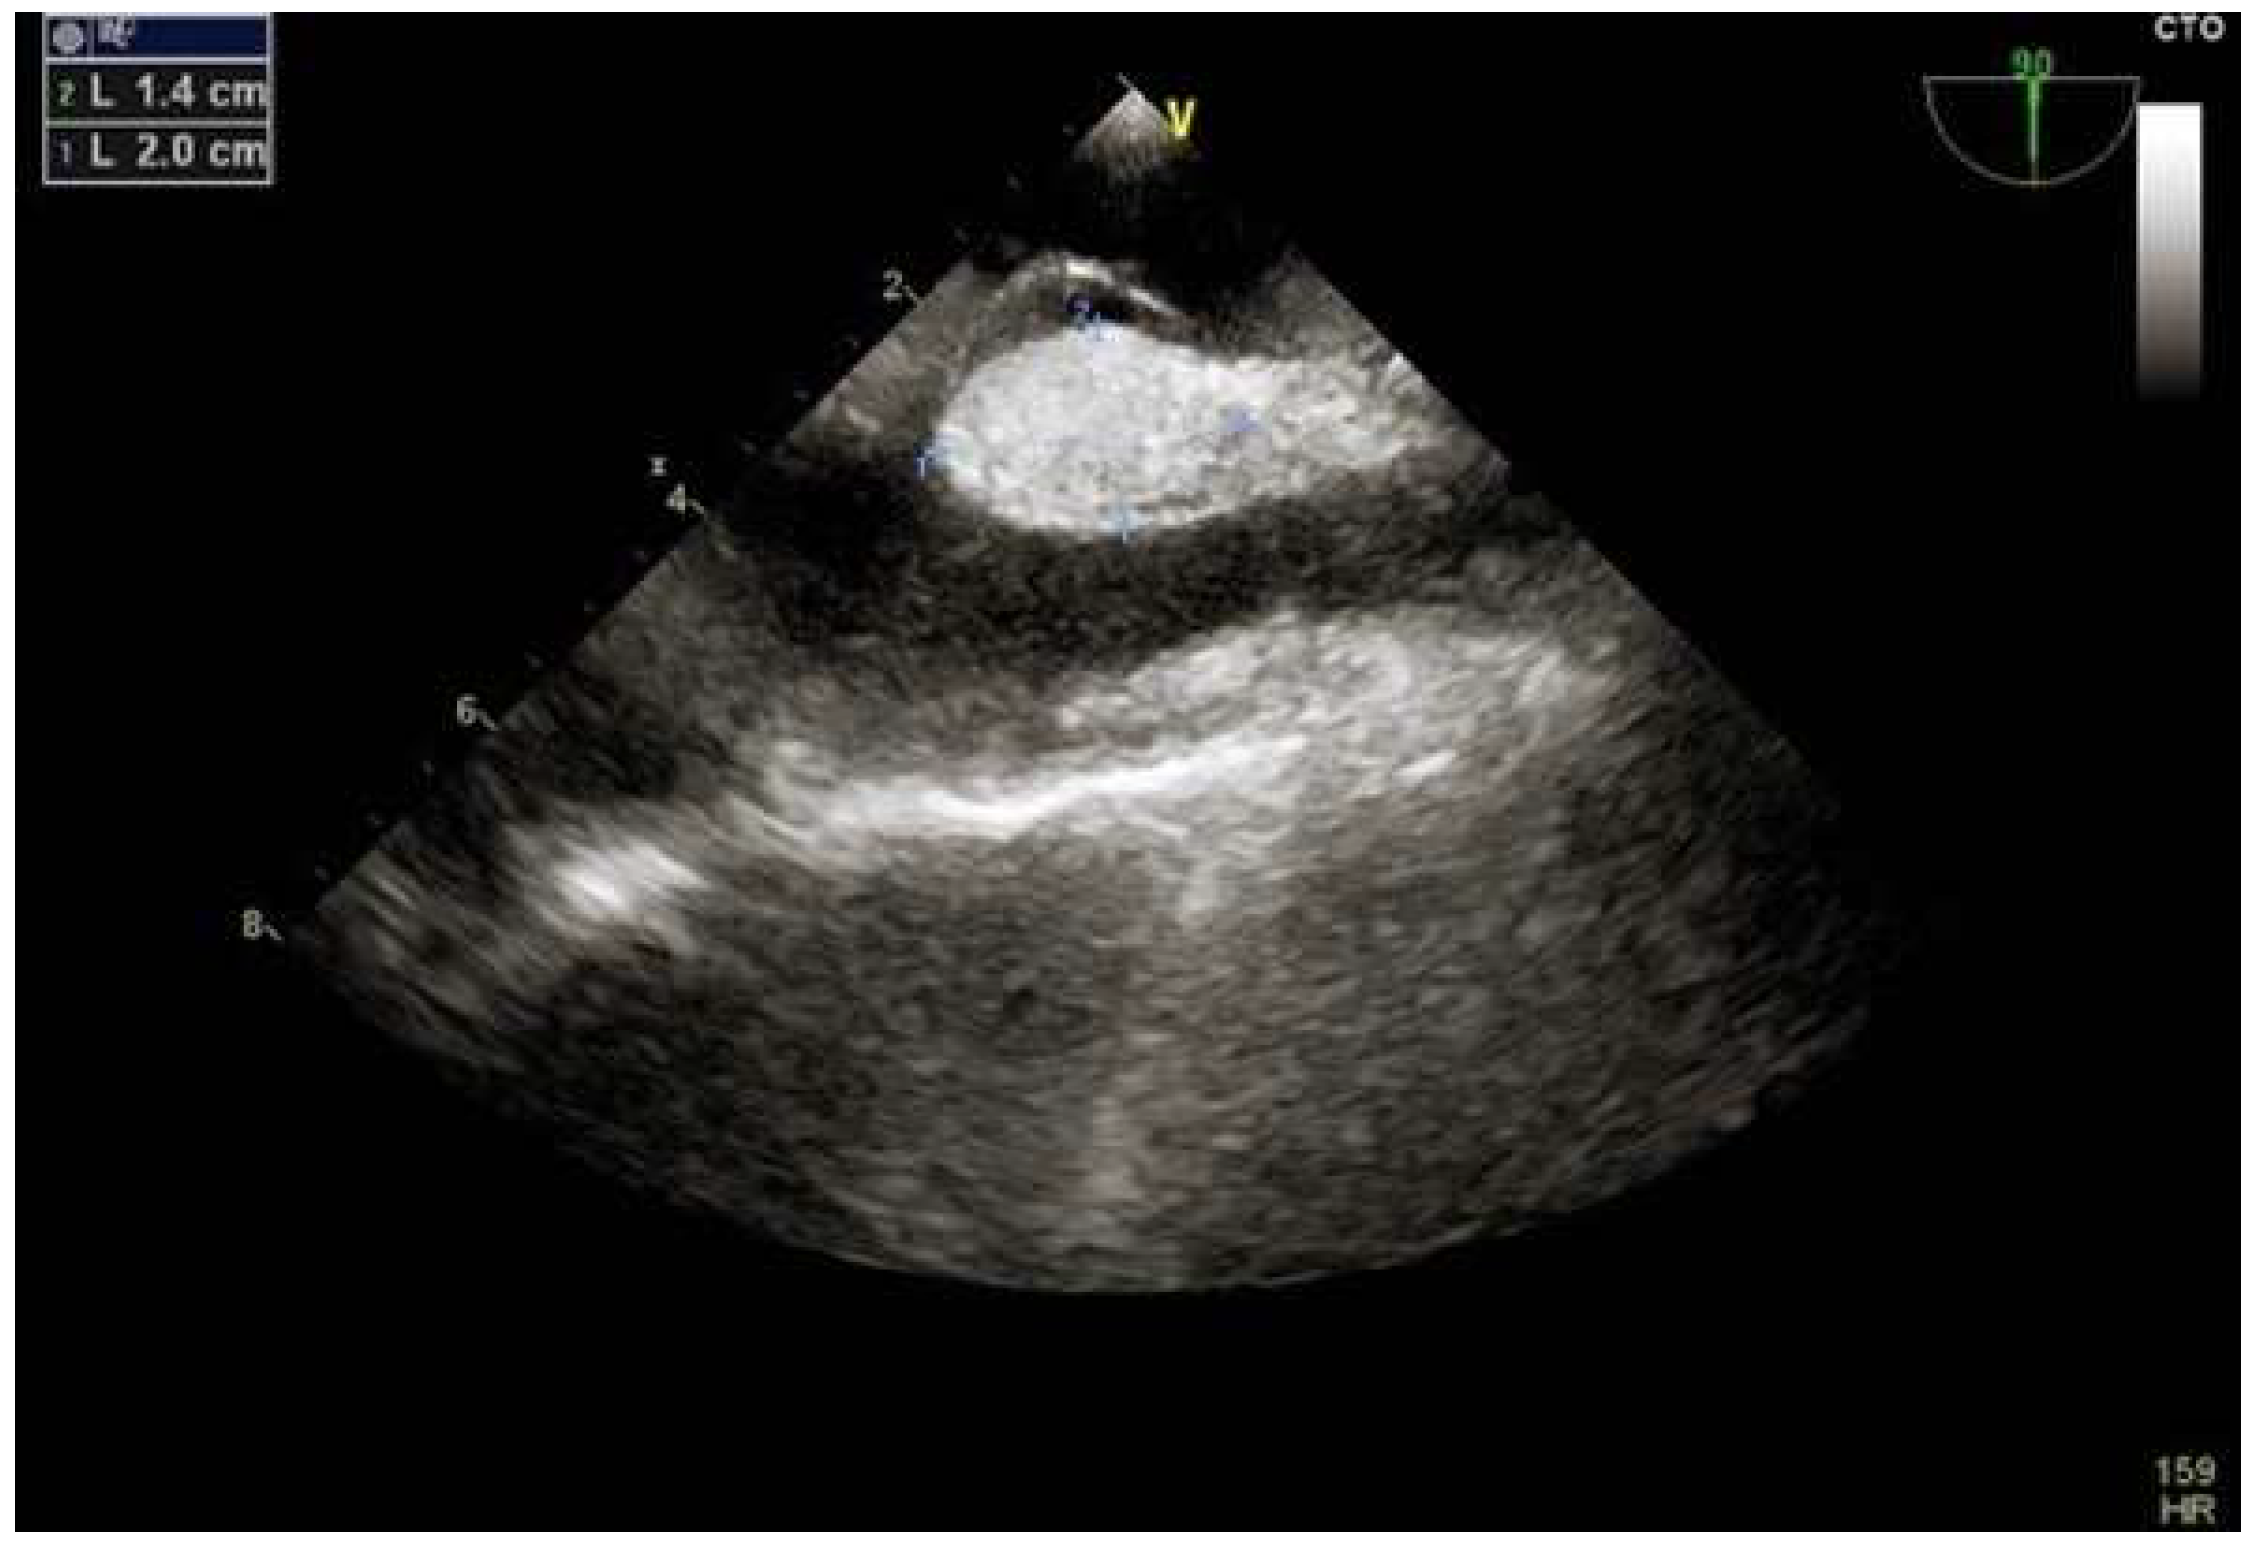

4. Percutaneous Closure of PFO by Novel Devices: The NobleStitch

4.2. Role of TEE